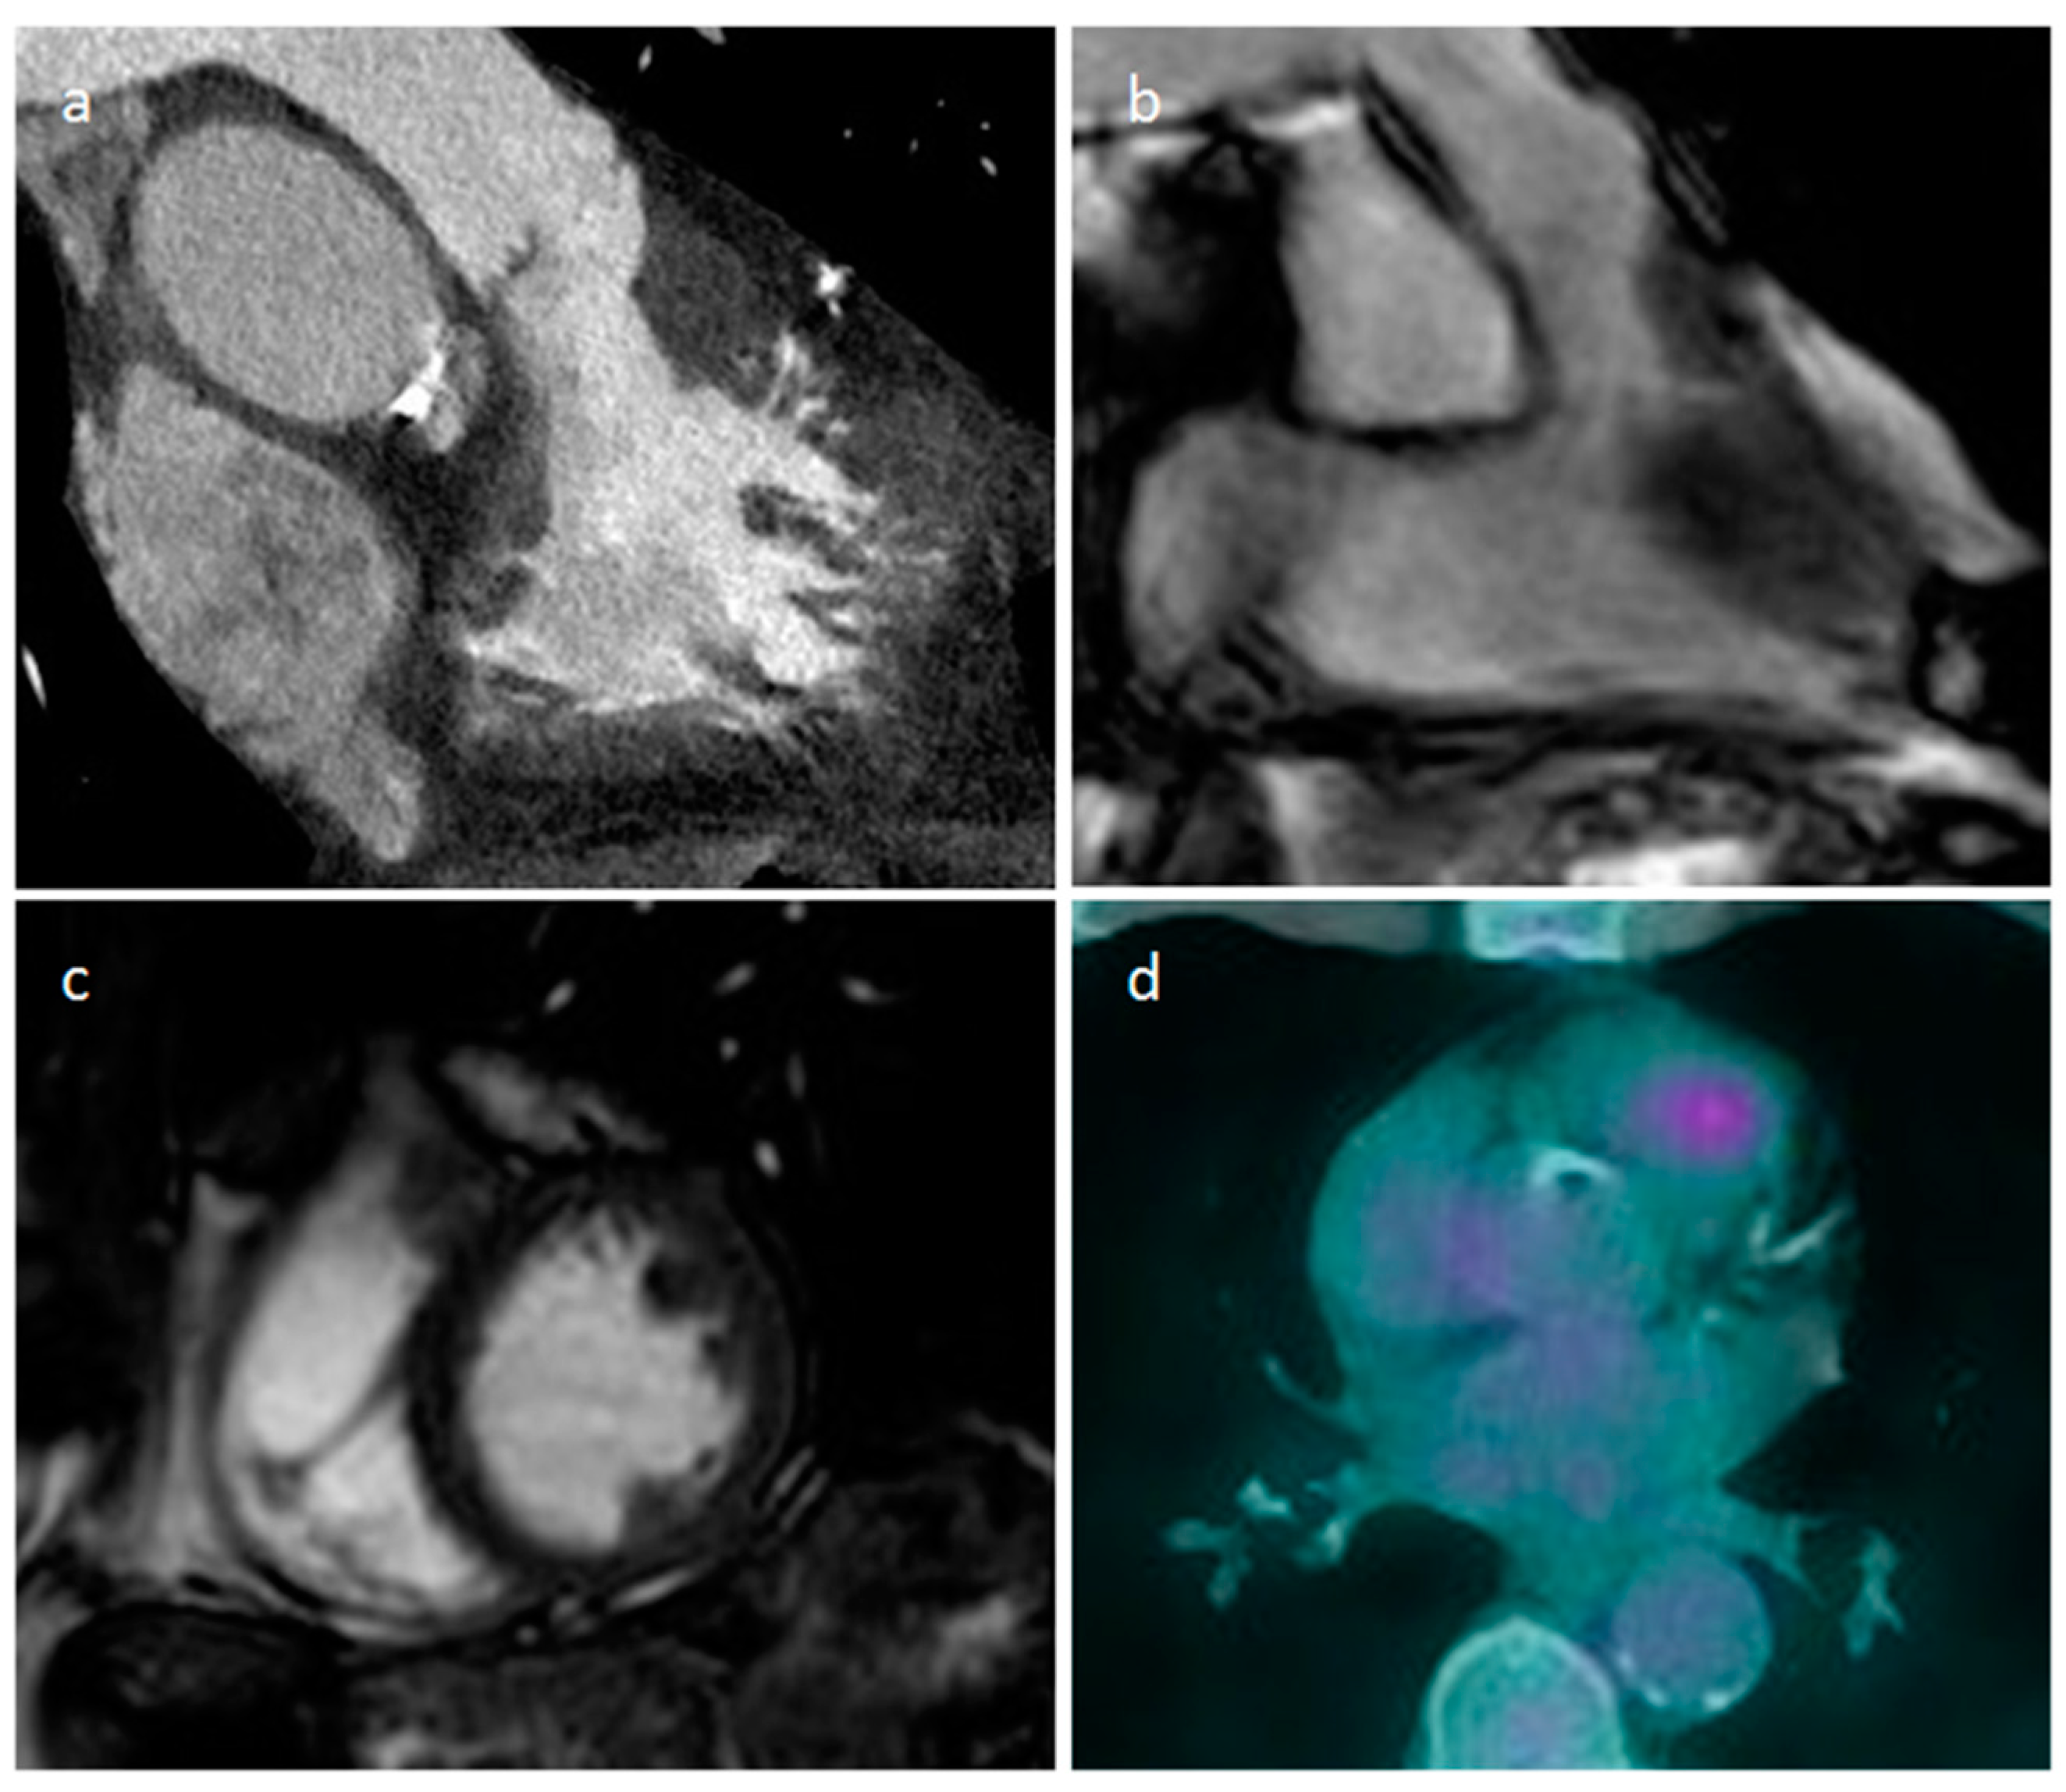

5.1. Secondary Tumors-Metastasis

| Metastasis | Adulthood Melanoma, lung, breast and esophageal cancers common. Transvenous: HCC and RCC | Myocardium, pericardium, right atrium in transvenous spread | Flow obstruction/heart failure, arrhythmia, pericardial effusion | Multiple myocardial or pericardial masses. Right atrium lesions in transvenous spread. More often circumscribed lesions | Heterogeneous, highly echogenic with contrast infusion | Similar to soft tissue attenuation | Hypo-iso T1w, Iso-hyper T2w, heterogeneous LGE. Melanoma: hyper T1w |